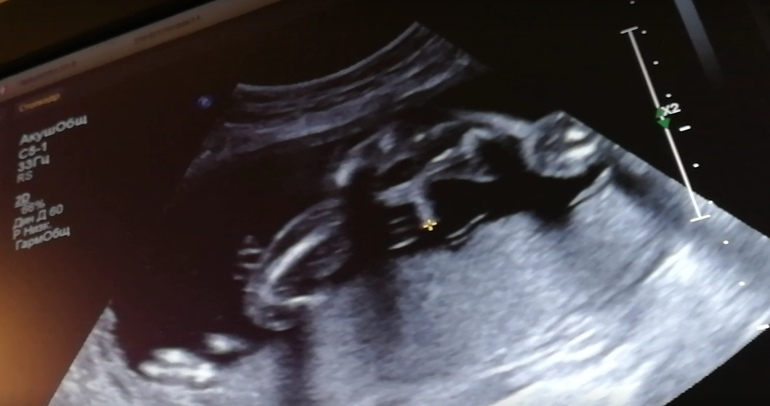

Второй скрининг пройден, ура

У нас все хорошо, писюн не отвалился) сказали, уже и не отвалится))

Очень хороший скрининг!)

У нас на одной почке лоханка увеличена, но это наследственное)